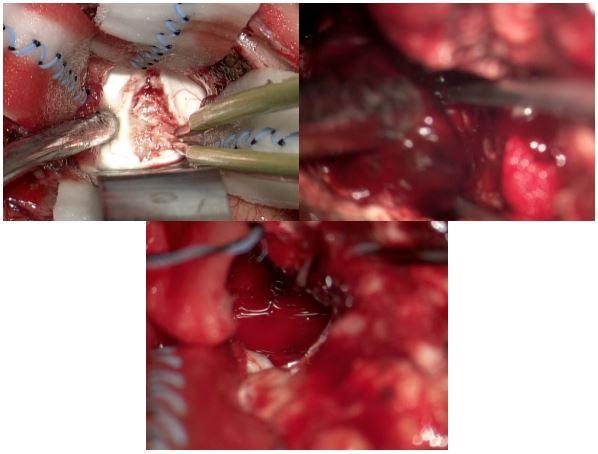

图2:

左上:切开丘脑枕,见肿瘤色红、质韧、血供丰富;

右上:切除肿瘤过程中,瘤体色紫红,血供极其丰富,出血凶猛;

下:术中急性脑膨出、无搏动,术腔迅速缩小,超声提示右侧脑室血肿铸型。